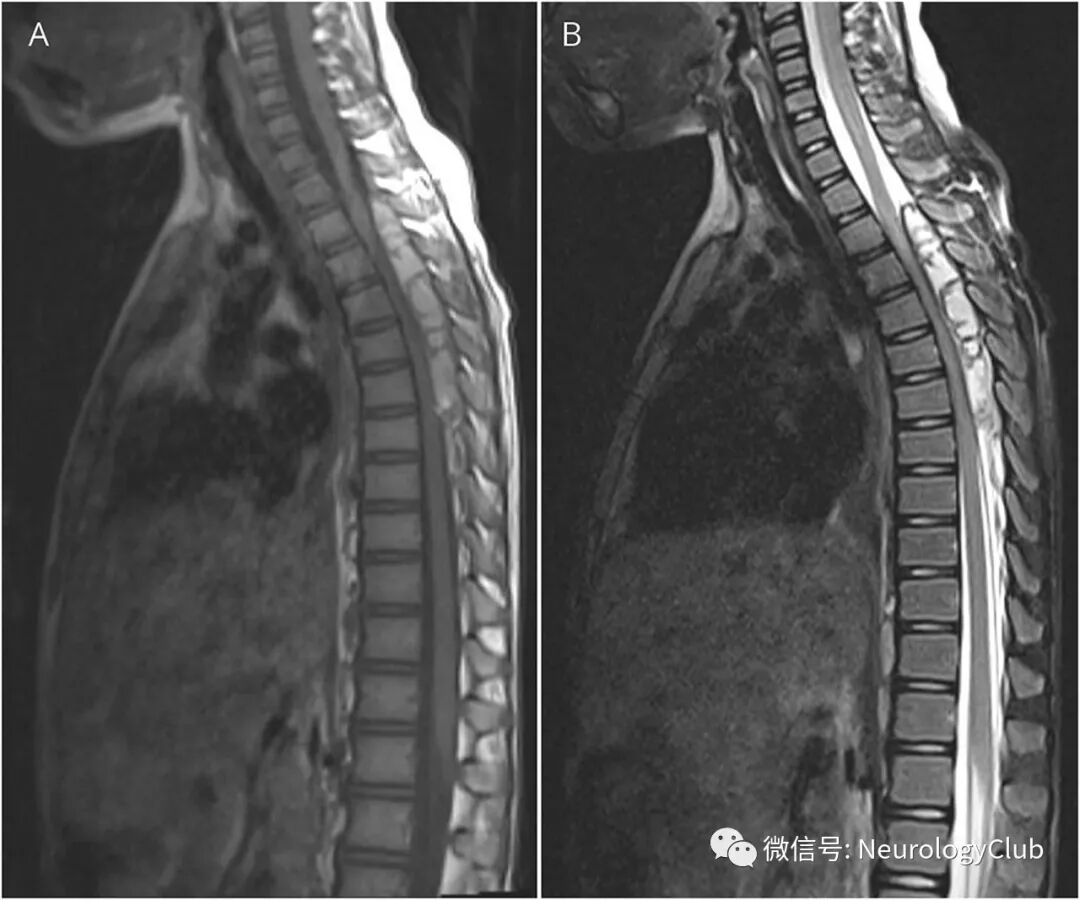

7岁女孩,表现为双腿进行性无力和感觉异常1周。脊髓矢状位MRI可见T3-T8水平一大的硬膜外血肿伴病灶内分隔(图1)。横断面上,病灶从左侧椎间孔延伸至椎旁区域,并与增厚的左侧胸膜融合(图2)。MRI可见多发肺内结节。

(图1:A:T1WI;B:T2WI;可见T3-T8水平一巨大的高信号椎管内肿块伴病灶内分隔;脊髓严重受压)